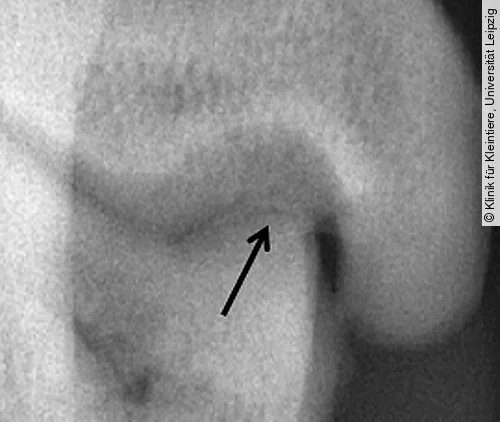

Projektionsradiografie Tarsokruralgelenk

Standardmäßig werden zur Projektion des Tarsalgelenks eine mediolaterale und eine dorsoplantare/plantodorsale Aufnahme angefertigt. Besteht der klinische Verdacht einer OCD und lassen sich auf den genannten Projektionen aber keine Hinweise dafür feststellen, werden dorsoplantare Aufnahmen mit Flexion des Tarsus angeraten (Skyline) [1], [22].

Häufig ist eine Abflachung des medialen Talusrollkamms im Sinne eines subchondralen Knochendefekts zu erkennen; seltener auch des lateralen Rollkamms. Im Bereich des Defekts ist im Falle einer Mineralisation eine isolierte Knorpelschuppe zu erkennen. Die schnell einsetzende, meist hochgradige Arthrose führt zusätzlich zu einer unruhigen proximalen Kontur (Abb. [ 9 ]). Ein weiterer Hinweis ist ein erweiterter medialer Gelenkspalt des Tarsokruralgelenks [1], [18], [22]. Mithilfe der Computertomografie können Ausmaß und Lokalisation der Defekte jedoch weitaus sicherer dargestellt werden [11].